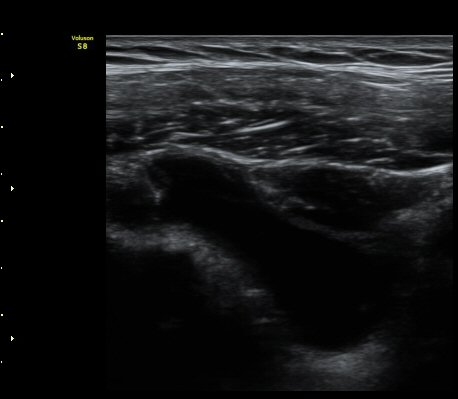

10ÀÏ ÈÄ ÃßÀû°Ë»ç

3°³¿ù ÈÄ ÃßÀû°Ë»ç

2049205267_d4912430_US181205109.jpg